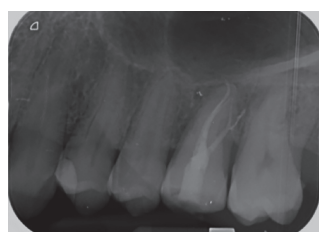

Caso clínico: se presenta el caso de un varón de 28 años, que acudió a consulta por la presencia de unos restos radiculares en localización de primer molar superior izquierdo. Se realizó un autotrasplante dental, siendo el diente donante el tercer molar superior izquierdo, que se trasplantó al alveolo del primer molar, mostrando buena evolución clínica y radiográfi ca.

Clinical case: a clinical case of a 28-yearold man is presented, who went to dental clinic for removal of left fi rst molar roots. An autotransplant was performed using left third molar as donor tooth, which was transplanted into fi rst molar alveolus, showing promising clinical and radiographic evolution.

Por tanto, debido a las altas tasas de éxito descritas en la literatura, el objetivo del presente caso clínico es evaluar clínica y radiográficamente la realización de un autotrasplante con el ápice cerrado, para reponer un primer molar superior izquierdo, como alternativa terapéutica a la colocación de un implante en un paciente adulto.